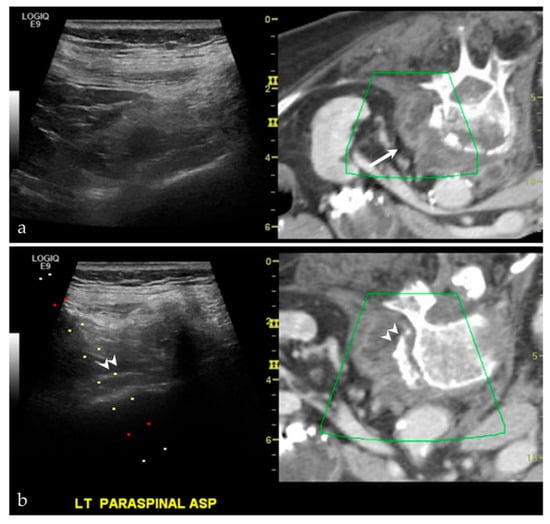

3.2.4. Targeted Percutaneous Lesion Biopsy and/or Aspiration

| NA/NA | Left paraspinal region | US-CT | Metastatic disease, unknown carcinoma | Neoplastic, malignant |

| 17/M | Acromioclavicular joint | US-MRI | Metastatic disease, nasopharyngeal carcinoma | Neoplastic, malignant |